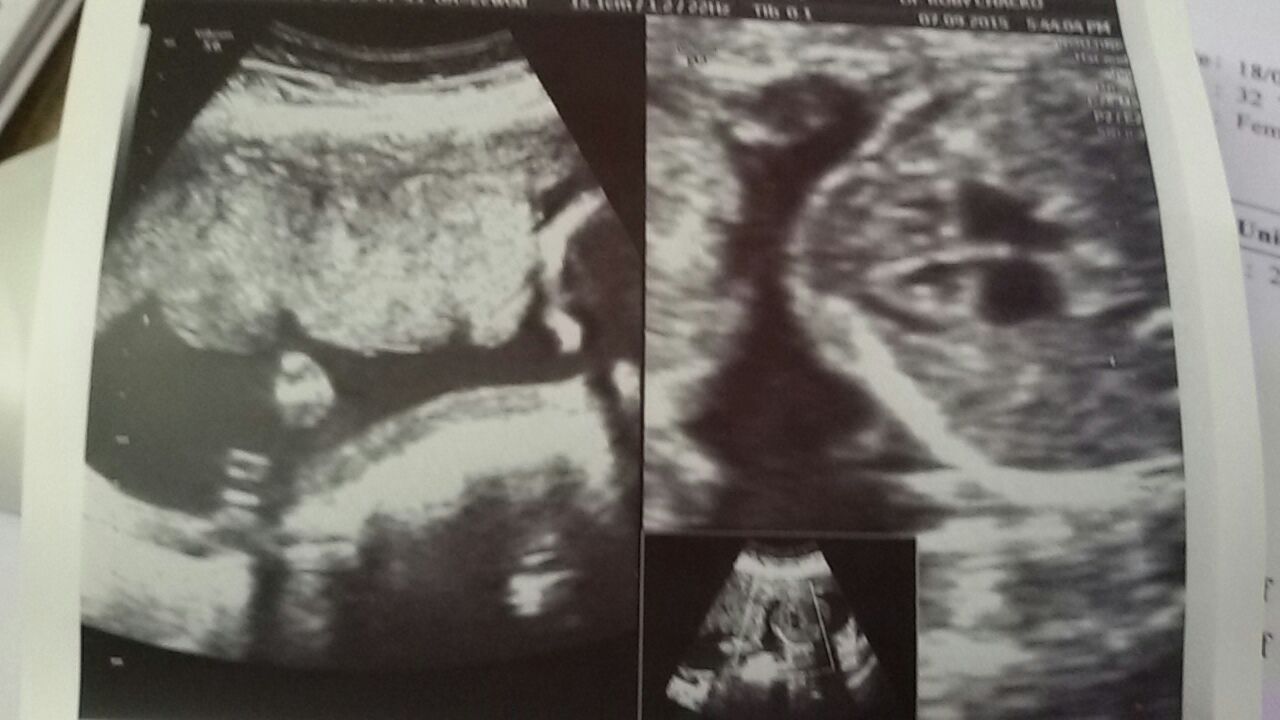

well my clinic won't disclose gender :( :mad:

Even at 22 weeks???!!! That is crazy!

Oh no what a nightmare! Go private! X